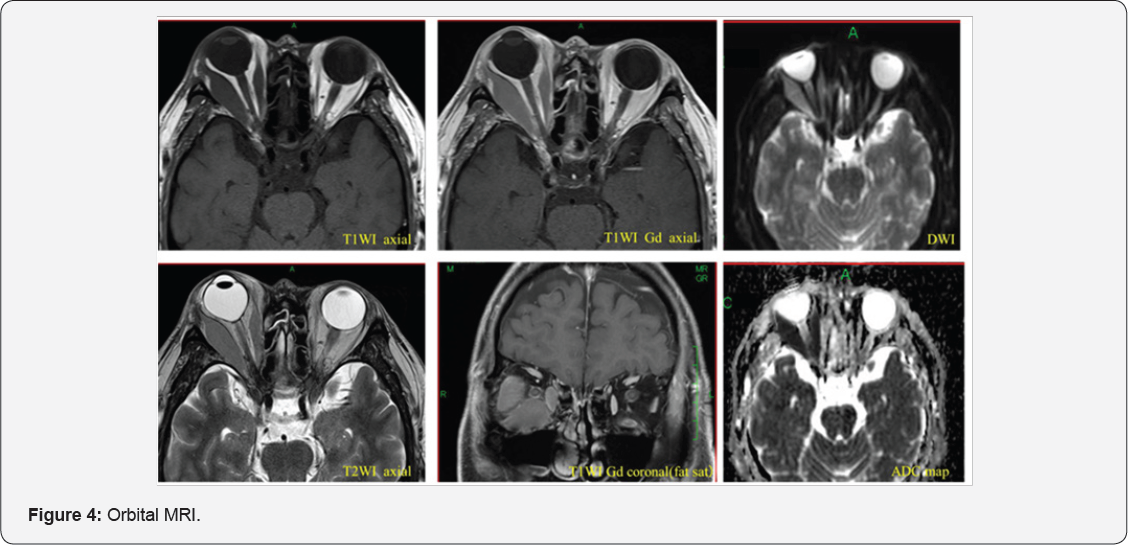

A 60-year-old man was examined because of blurred vision in the right eye. The right eye exhibited an ocular motility disorder in all directions. Three days later, he was referred to our department. His medical history included acute ATLL diagnosed 2 years earlier, with complete remission after chemotherapy. He also had a thyroid adenoma, which was diagnosed by biopsy. The findings at initial examination were as follows, corrected visual acuities20/20 OU, pupil diameters, 5 and 6mm in the dark and 3 and 3mm in room light, for the right and left eyes, respectively. The pupillary light reflex was rapid and complete, and the relative afferent pupillary defect (RAPD) was negative. Before the use of 1% apraclonidine eye drops, the pupil diameters of the right and left eyes were7 and 6mm, respectively. The right eye exhibited restricted abduction and depression as well as exophthalmos (Figure 1). Hertel exophthalmometer was 24mm OD, 19mm OS. The force deduction test was positive. No abnormalities were in the anterior ocular segment, optic media, or ocular fundus. His plane MRI showed swelling of the lateral rectus and inferior rectus muscles of the right eye (Figure 2). Orbital diseases in the right eye, such as thyroid eye disease, orbital myositis, and Horner syndrome were thought to be affecting the thyroid adenoma biopsy. One month later, the symptoms worsened. His corrected visual acuities 20/60 OD, 20/20 OS and right-eye RAPD was detected. In addition, chemosis, increased intraocular pressure, and optic disc swelling were observed (Figure 3). Thus, the patient was emergently admitted to our hospital. Enhanced orbital MRI showed the right medial rectus, lateral rectus, and inferior rectus muscles were more swelling. These muscles compressed the optic nerve at the orbital apex. The muscles were hypo intense on T1-weighted images and hyper intense on T2-weighted images, and showed a uniform enhancement effect. Diffusion-weighted images (DWI) showed hyper intense signals, and the apparent diffusion coefficient value was markedly low at 0.5. (Figure 4), suggestive of malignant lymphoma. We did biopsy of the inferior rectus muscle (Figure 5). Histpathologically, there was diffuse proliferation of lymphocytes containing small to large nuclei. Immunostaining tested positive for CD3 and CD4, and negative for CD8 and CD79a (Figure 6). Consequently, he diagnosed with ATLL cellular infiltration and recurrence of ATLL.

MRI shows swelling of the right medial rectus, lateral rectus, inferior rectus muscles, and compression of the optic nerve at the orbital apex. Low intensity signals were recorded on T1-weighted images of the muscles and high intensity signals on T2-weighted images of the muscles with uniform intensity.

High intensity signals occurred on diffusion-weighted images, and the apparent diffusion coefficient was markedly low at 0.5, suggestive of malignant lymphoma.